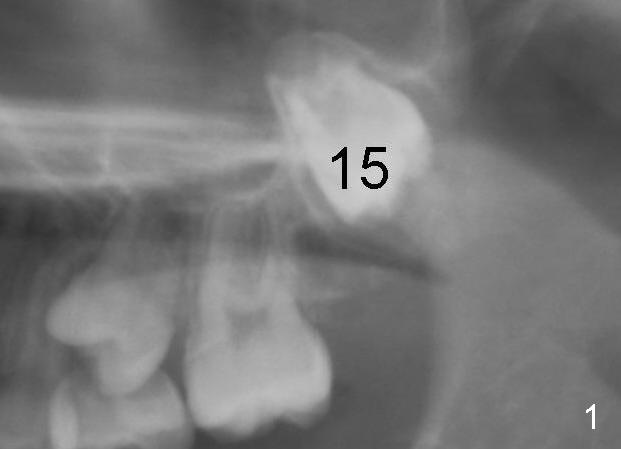

When the female patient was 11 years 2 months (Fig.1) and 12 years 10 months (Fig.2) old, the eruption of #15 is delayed. The tooth is surgically uncovered with bonding an eruption chain 1 month post banding. Three (Fig.3), 4 (Fig.4) and 6 (Fig.5) months post banding, eruption appears to be slow with elastics.